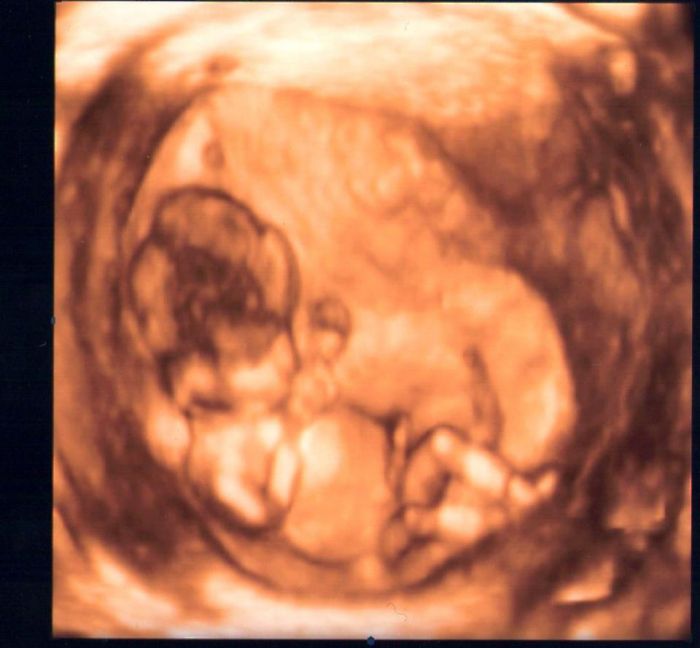

.Jdu 3.5. na ultrazvuk,tak se nemůžu dočkat.Jinak mám doma kluka i holku,tak mi to je jedno,co to bude.Strašně ráda pozoruji,jak se fazolka vrtí...Včera to konečně cejtil i můj přítel...ultrazvuk je ze 3měsíce.